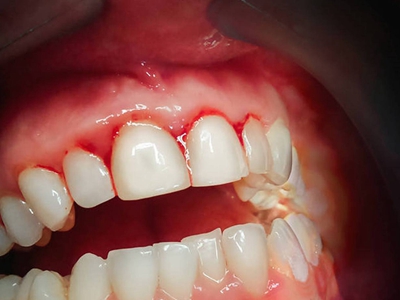

牙龈

红肿

戈登热牙龈红肿出血图

登革热患者可以发生不同程度的出血现象,包括牙龈红肿出血,牙龈边缘渗出鲜红色的血液,同时可伴有发热、头痛、肌肉及关节痛、极度乏力、恶心、呕吐等症状。

充血

戈登热牙龈充血牙齿上带血图

登革热会使毛细血管通透性增加导致明显的血浆渗出,出现牙齿上带血,也可能导致其他情况的出血情况,比如皮下出血、注射部位瘀点瘀斑、鼻出血等。

出血

登革热牙龈出血图

登革热患者会出现不同程度的出血现象,可表现为牙龈出血,多为鲜红色,出血量一般较少,牙龈多无红肿。患者常伴有高热、头痛、呕吐、腹泻等全身症状。